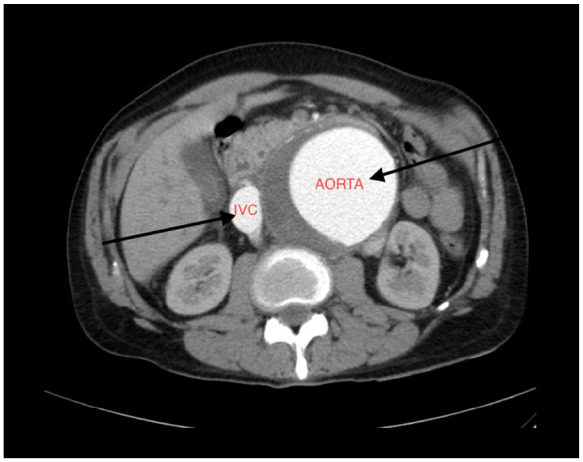

Abdominal aortic aneurysm (AAA) is a potentially life-threatening condition characterized by abnormal dilation of the abdominal aorta, typically due to chronic arterial wall degeneration. Aorto-caval fistula (ACF) is a rare but serious complication of AAA, occurring in less than 1% of cases overall, with incidence increasing in the setting of rupture. ACF involves the formation of an abnormal communication between the abdominal aorta and the inferior vena cava (IVC), resulting in blood shunting from the arterial to the venous system. This can cause reduced organ perfusion, high-output cardiac failure, and multiorgan dysfunction. We present the case of a 65-year-old hypertensive male with a known AAA who presented with 2 days of abdominal pain but no systemic or gastrointestinal symptoms. Physical examination revealed periumbilical tenderness, while laboratory results were normal. Contrast-enhanced computed tomography of the abdomen revealed a large (10 cm) infrarenal AAA with evidence of rupture, mural thrombus, and a fistulous connection to the IVC. The patient underwent successful endovascular repair with complete resolution of the aneurysm and fistula, as shown in follow-up imaging. This case highlights the importance of high clinical suspicion and the role of early imaging in diagnosing ACFs, even in the absence of classical signs or lab abnormalities. The aim is to raise awareness of such atypical presentations and emphasize our case's uniqueness in its silent, stable, yet severe presentation.

Abstract Image